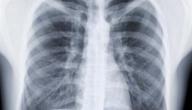

• الأشعة السينية للجلد: يبحث الأخصائي عن بقعٍ صغيرة موجودة في الرئة، فهذه البقع تدل على على إصابة الشخص بمرض السل.